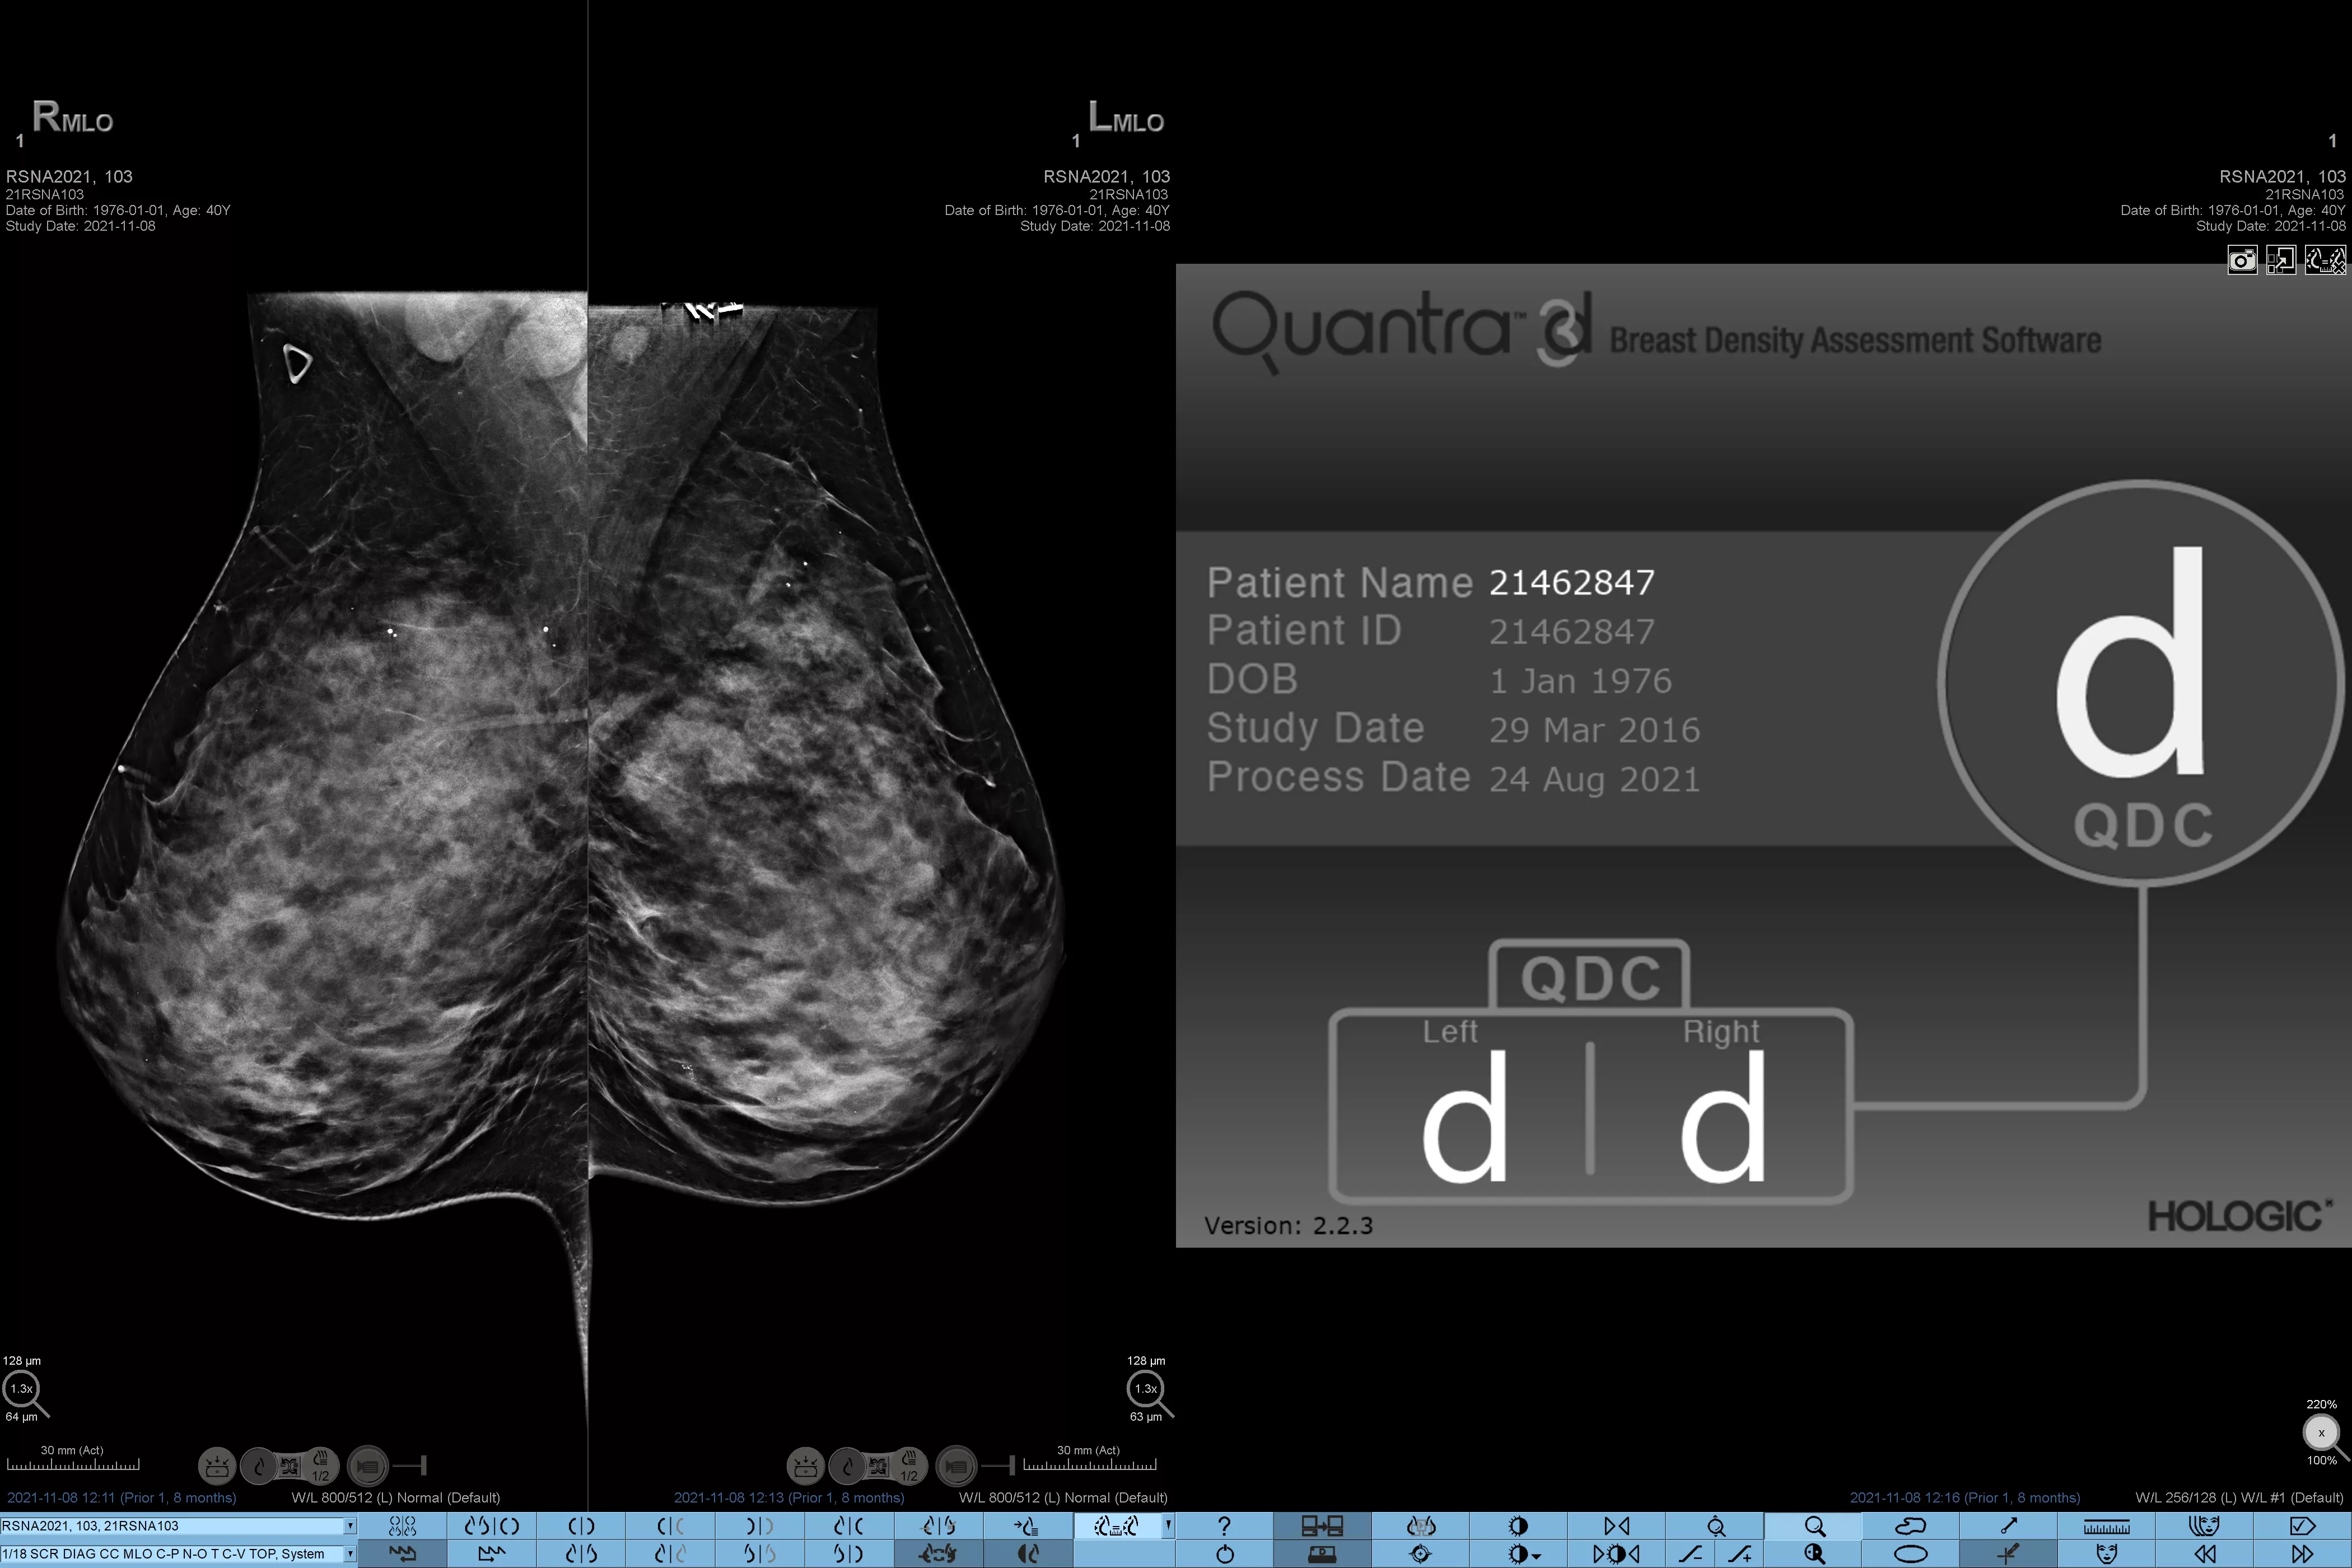

Higher breast density is known to increase a woman’s risk for breast cancer.1 The need for accurate, unbiased analysis is therefore critical. Powered by machine learning, Quantra technology software analyses both 2D™ and tomosynthesis images for distribution and texture of parenchymal tissue. It categorises breasts in four breast composition categories consistent with guidance from the American College of Radiology (ACR) BI-RADS Atlas 5th Edition.2

Breast imaging scans

8. Breast composition categories as described in ACR BI-RADS Atlas.